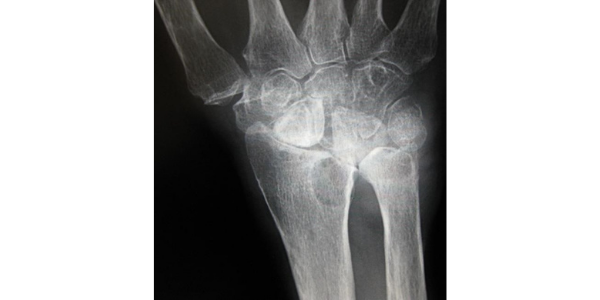

Chụp X-quang.

Tia X cung cấp hình ảnh chi tiết của các cấu trúc dày đặc, chẳng hạn như xương. Chụp X-quang cổ tay sẽ giúp bác sĩ tìm hiểu thêm về vị trí chính xác và mức độ nghiêm trọng của bệnh viêm khớp. Họ cũng có thể giúp bác sĩ của bạn phân biệt giữa các loại viêm khớp khác nhau.